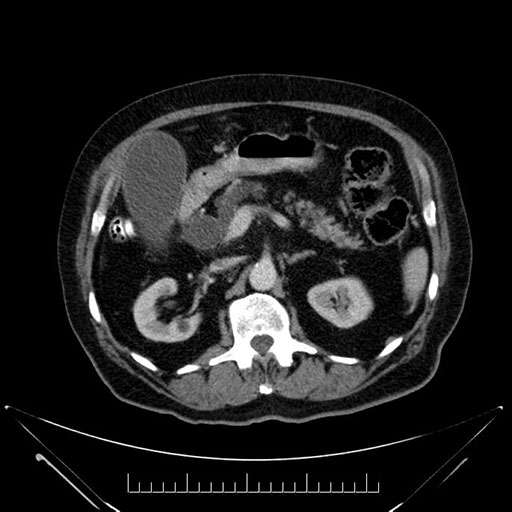

Imaging Analysis

Look through the patient's CT scan to identify any areas of concern for the necessary procedure.

Based on your CT findings, which issue(s) would give reason for "planned slowing down moment(s)" in this case?